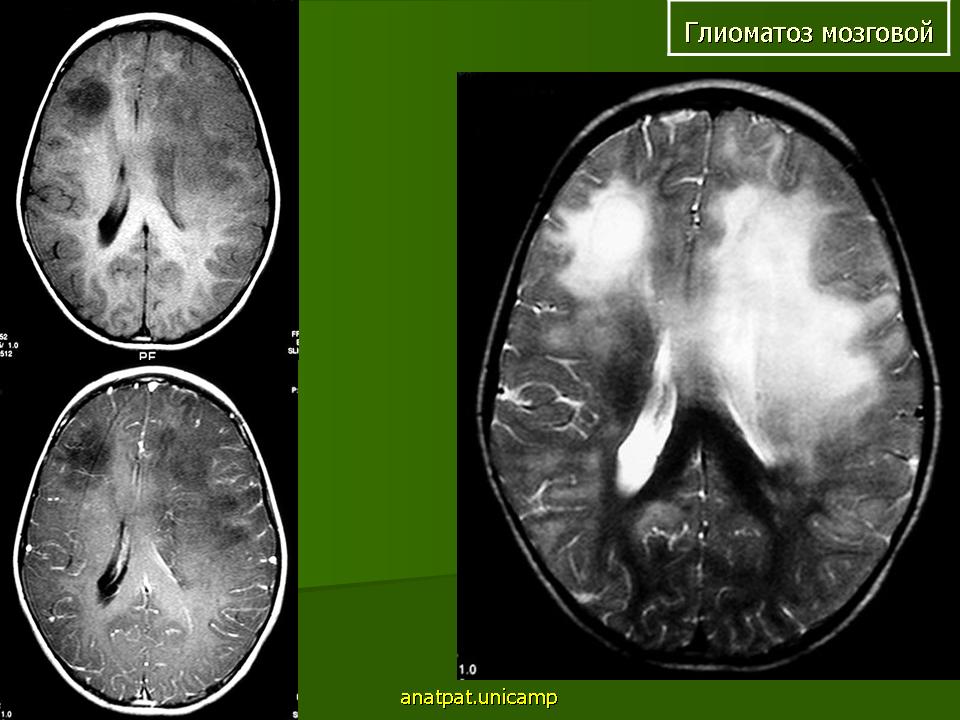

Глиоматоз мозговой. Ср, 03/09/2014 - 12:08 #1 Катенёв Валенти... Не на сайте Был на сайте: 7 лет 3 месяцев назад Зарегистрирован: 22.03.2008 - 22:15 Публикации: 54876 Продолжение.Приложения:

Продолжение.